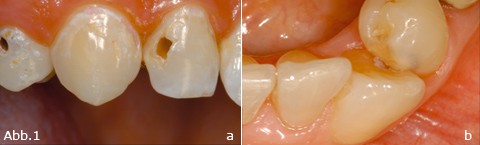

Die Karies (Abb.1) wird als multifaktorielles Geschehen angesehen, wobei die komplexe Ätiologie eine sichere Vorhersage aufgrund eines einzigen (einfachen) Tests nicht zulässt. Die Bestimmung des Kariesrisikos ist daher allenfalls mithilfe der Kombinationen mehrerer Informationen möglich. Hierzu zählen

Abb.1:  a: Aktive Läsionen mit zum Teil ausgeprägter Kavitation. b:  Karies zwischen 34 und 33 aufgrund eines Engstandes und erschwerter/unzureichender Mundhygiene.

Zur Berücksichtigung des Kariesrisikos ist der klinische Befund von besonderer Bedeutung. So lassen die Zahl der Zähne (Wann wurden Zähne extrahiert?), die Anzahl und Größe der Füllungen (Zeitpunkt und Häufigkeit der Erneuerung) sowie die Zahl der vorhandenen Demineralisationen oder sogar Kavitationen (Abb.1b) Rückschlüsse auf eine erhöhte Kariesaktivität zu. Der Zustand der Gingiva deutet auf eventuelle Mängel bei der Mundhygiene hin; auch das gleichzeitige Vorliegen erschwerender Umstände (Engstände, anatomische Besonderheiten, Füllungsüber-/unterschüsse, kieferorthopädische Behandlung) deutet auf ein erhöhtes Kariesrisiko hin.